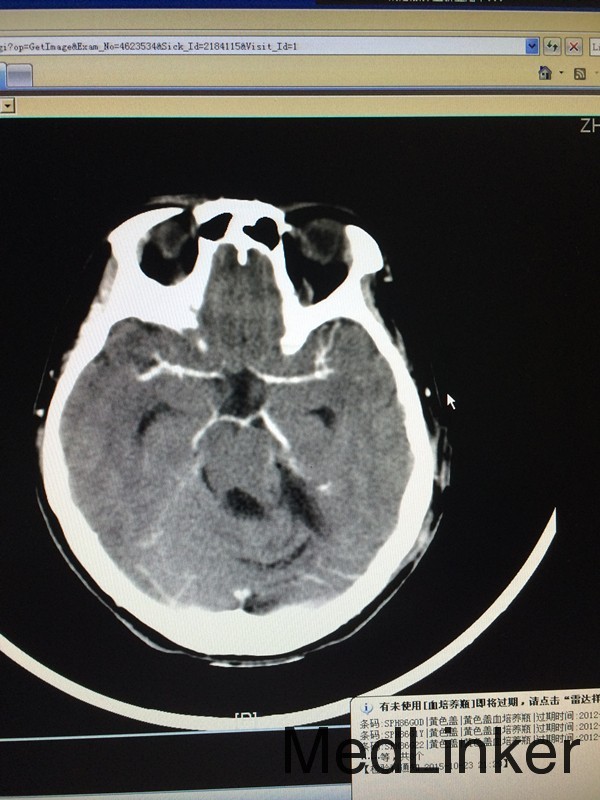

查体:左侧轻微面瘫,左侧面部感觉稍减退,余无特殊 辅助检查:头颅CT提示左侧桥小脑角区类圆形肿物,考虑听神经瘤可能,四脑室受压变窄并右移

诊断:左侧听神经瘤 治疗:行左侧桥小脑角区占位切除术,术后病理提示左侧桥小脑角神经鞘瘤